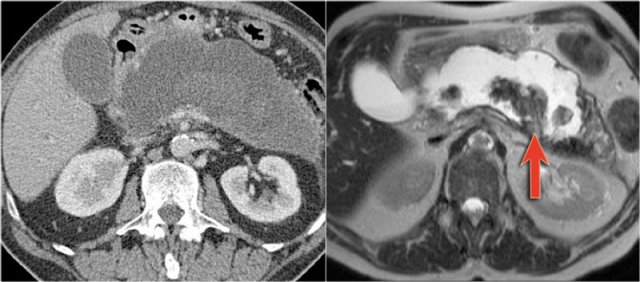

MRI shows a lesion, which consists of multiple small cysts.

This could be a serous cystic neoplasm or a branch-duct IPMN.

The connection of the cystic lesion to the pancreatic duct indicates that this is a branch-duct IPMN.